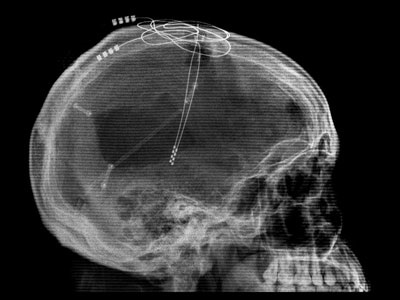

Pentru gaura de stimulare a creierului unilaterală este făcută în partea de sus a craniului. stimularea bilaterală a creierului necesită două găuri. anestezic puternic este folosit pentru a amorti toloko pielii la perforarea găuri. Deoarece creierul nu exista receptori de durere, iar atunci nu este nevoie de o anestezie mai profundă. În plus, pacientul trebuie ținut cont de faptul de a informa orice modificări organoleptice în timpul funcționării. Electrodul este amplasat foarte aproape de o serie de structuri importante ale creierului. Modificări organoleptice în timpul plasării electrodului poate indica faptul că el este prea aproape de una sau mai multe din aceste regiuni.

După ce gaura se face, chirurgul introduce electrodul. curentului electric mic din electrodul este folosit pentru localizare mai precisă. Această procedură este inofensiv, dar poate provoca spasme, flash-uri de lumină sau alte senzații. Colorantul de contrast poate fi injectat în lichidul cefalorahidian, acest lucru permite chirurgului să vizualizeze structura creierului folosind una sau mai multe metode imagistice.

Firul electrodului este conectat cu generatorul de impulsuri implantat. Acest fir este plasat sub scalp. un generator de impulsuri situat într-o mică incizie în zona claviculei. Această parte a procedurii se realizează sub anestezie generală.

Pacientul trece prin diferite teste medicale, precum și proceduri de unul sau mai multe tipuri de neuroimagistice, inclusiv RMN, CT, angiografia (imagistica a vaselor de sânge ale creierului) și ventriculografie (ventricule de vizualizare a imaginii). În ziua intervenției chirurgicale cadru stereotactica este atașat la capul pacientului. RMN-ul final a fost ținut cu cadrul stabilit pentru a determina coordonatele zonei țintă a creierului.